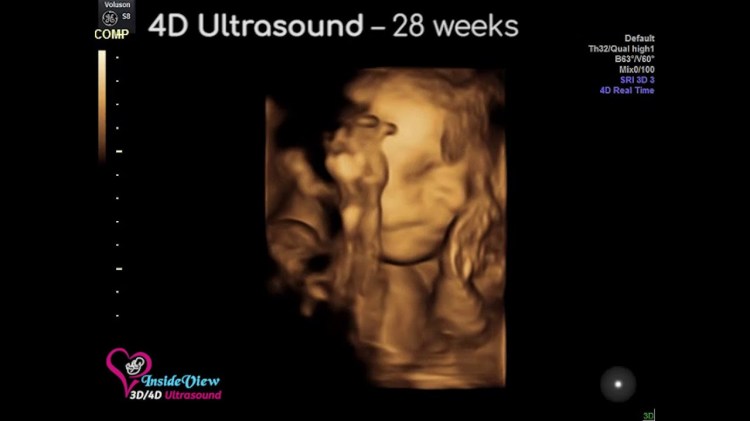

Es natural emocionarse al ver los resultados de su primera prueba de ultrasonido de embarazo. Los escaneos 3D ayudan a obtener imágenes fijas del bebé en tres dimensiones durante el embarazo. Al mismo tiempo, la ecografía 4D muestra imágenes en 3D del bebé, siendo el tiempo la cuarta dimensión. Algunos padres pueden encontrar los escaneos 2D estándar un poco decepcionantes debido a su contorno gris y borroso. En la ecografía 3D y 4D, puede ver la piel de su bebé, la forma de su boca y nariz, o también puede detectar los bostezos del bebé. Las imágenes de ultrasonido 3D y 4D se obtienen de las secciones de imágenes 2D convertidas en una sola imagen y, por lo tanto, también son seguras. Estas pruebas pueden tardar entre 45 minutos y una hora. Los ultrasonidos 3D y 4D brindan más información sobre su bebé y también indican las anomalías (si las hay). Estos escaneos muestran más detalles que el ultrasonido 2D estándar; ayuda a los médicos a diagnosticar el labio hendido. Permite a los médicos planificar el tratamiento adecuado para reparar el labio hendido del bebé después de su nacimiento. También puede observar el corazón y otros órganos internos con la ayuda de ultrasonidos 3D.

El propósito de tener ecografías 3D

Se realiza una prueba de ultrasonido 3D (tercera dimensión) para obtener imágenes detalladas de un bebé. Las imágenes del escaneo 3D son de color naranja y dorado, lo que brinda detalles de los ojos, la nariz, la cara, la boca, etc. del bebé. También es útil para observar el corazón y otros órganos internos. Las clínicas que realizan escaneos 3D solo los hacen cuando es médicamente necesario.

El propósito de realizar ecografías 4D

Las ecografías 4D (cuatridimensionales) ayudan a capturar el video de su bebé en movimiento, bostezando o sonriendo al anochecer en el útero. La única diferencia entre los dos escaneos es que en el escaneo 3D se obtiene la imagen, mientras que en el escaneo 4D los resultados se muestran en un video real.

En este momento, su bebé se ha estado llenando muy bien. Es el momento ideal para obtener primeros planos del rostro del bebé con detalles únicos. Es más probable que el bebé esté con la cabeza hacia abajo, lo que hace que la visualización sea mucho más fácil. A medida que se acerca a la semana 40 de embarazo (semana 37 o posterior), obtener las imágenes faciales se vuelve un desafío porque el bebé crece demasiado y el útero está abarrotado. Pero como se mencionó anteriormente, no todos los embarazos son iguales. Entonces, hay momentos en que algunas madres cercanas a la semana 40 han logrado imágenes bellamente detalladas.